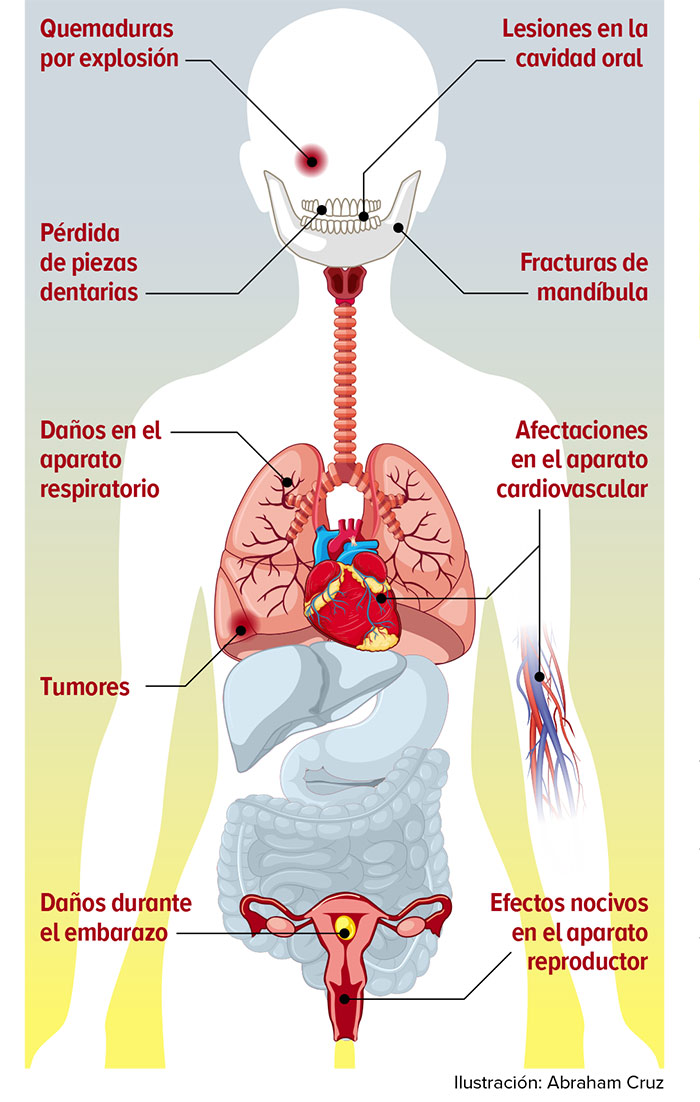

López Obrador firma decreto para prohibir el uso de vapeadores y cigarros electrónicos

México prohibió desde este martes el uso de vapeadores y cigarros electrónicos por los daños que causan a la salud, a través de un decreto…

Mientras un cigarro contiene un miligramo de nicotina, los sistemas pods de vapeo pueden llegar a tener hasta 60 miligramos, lo que equivaldría a tres…